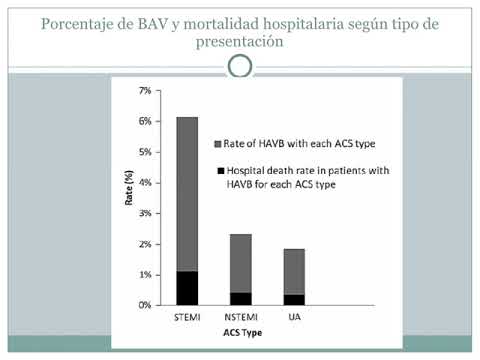

Bloqueos AV de alto grado en los SCA. Dr. Maximiliano G. Mascarello. Residencia de Cardiología. Hospital C. Argerich. Buenos Aires